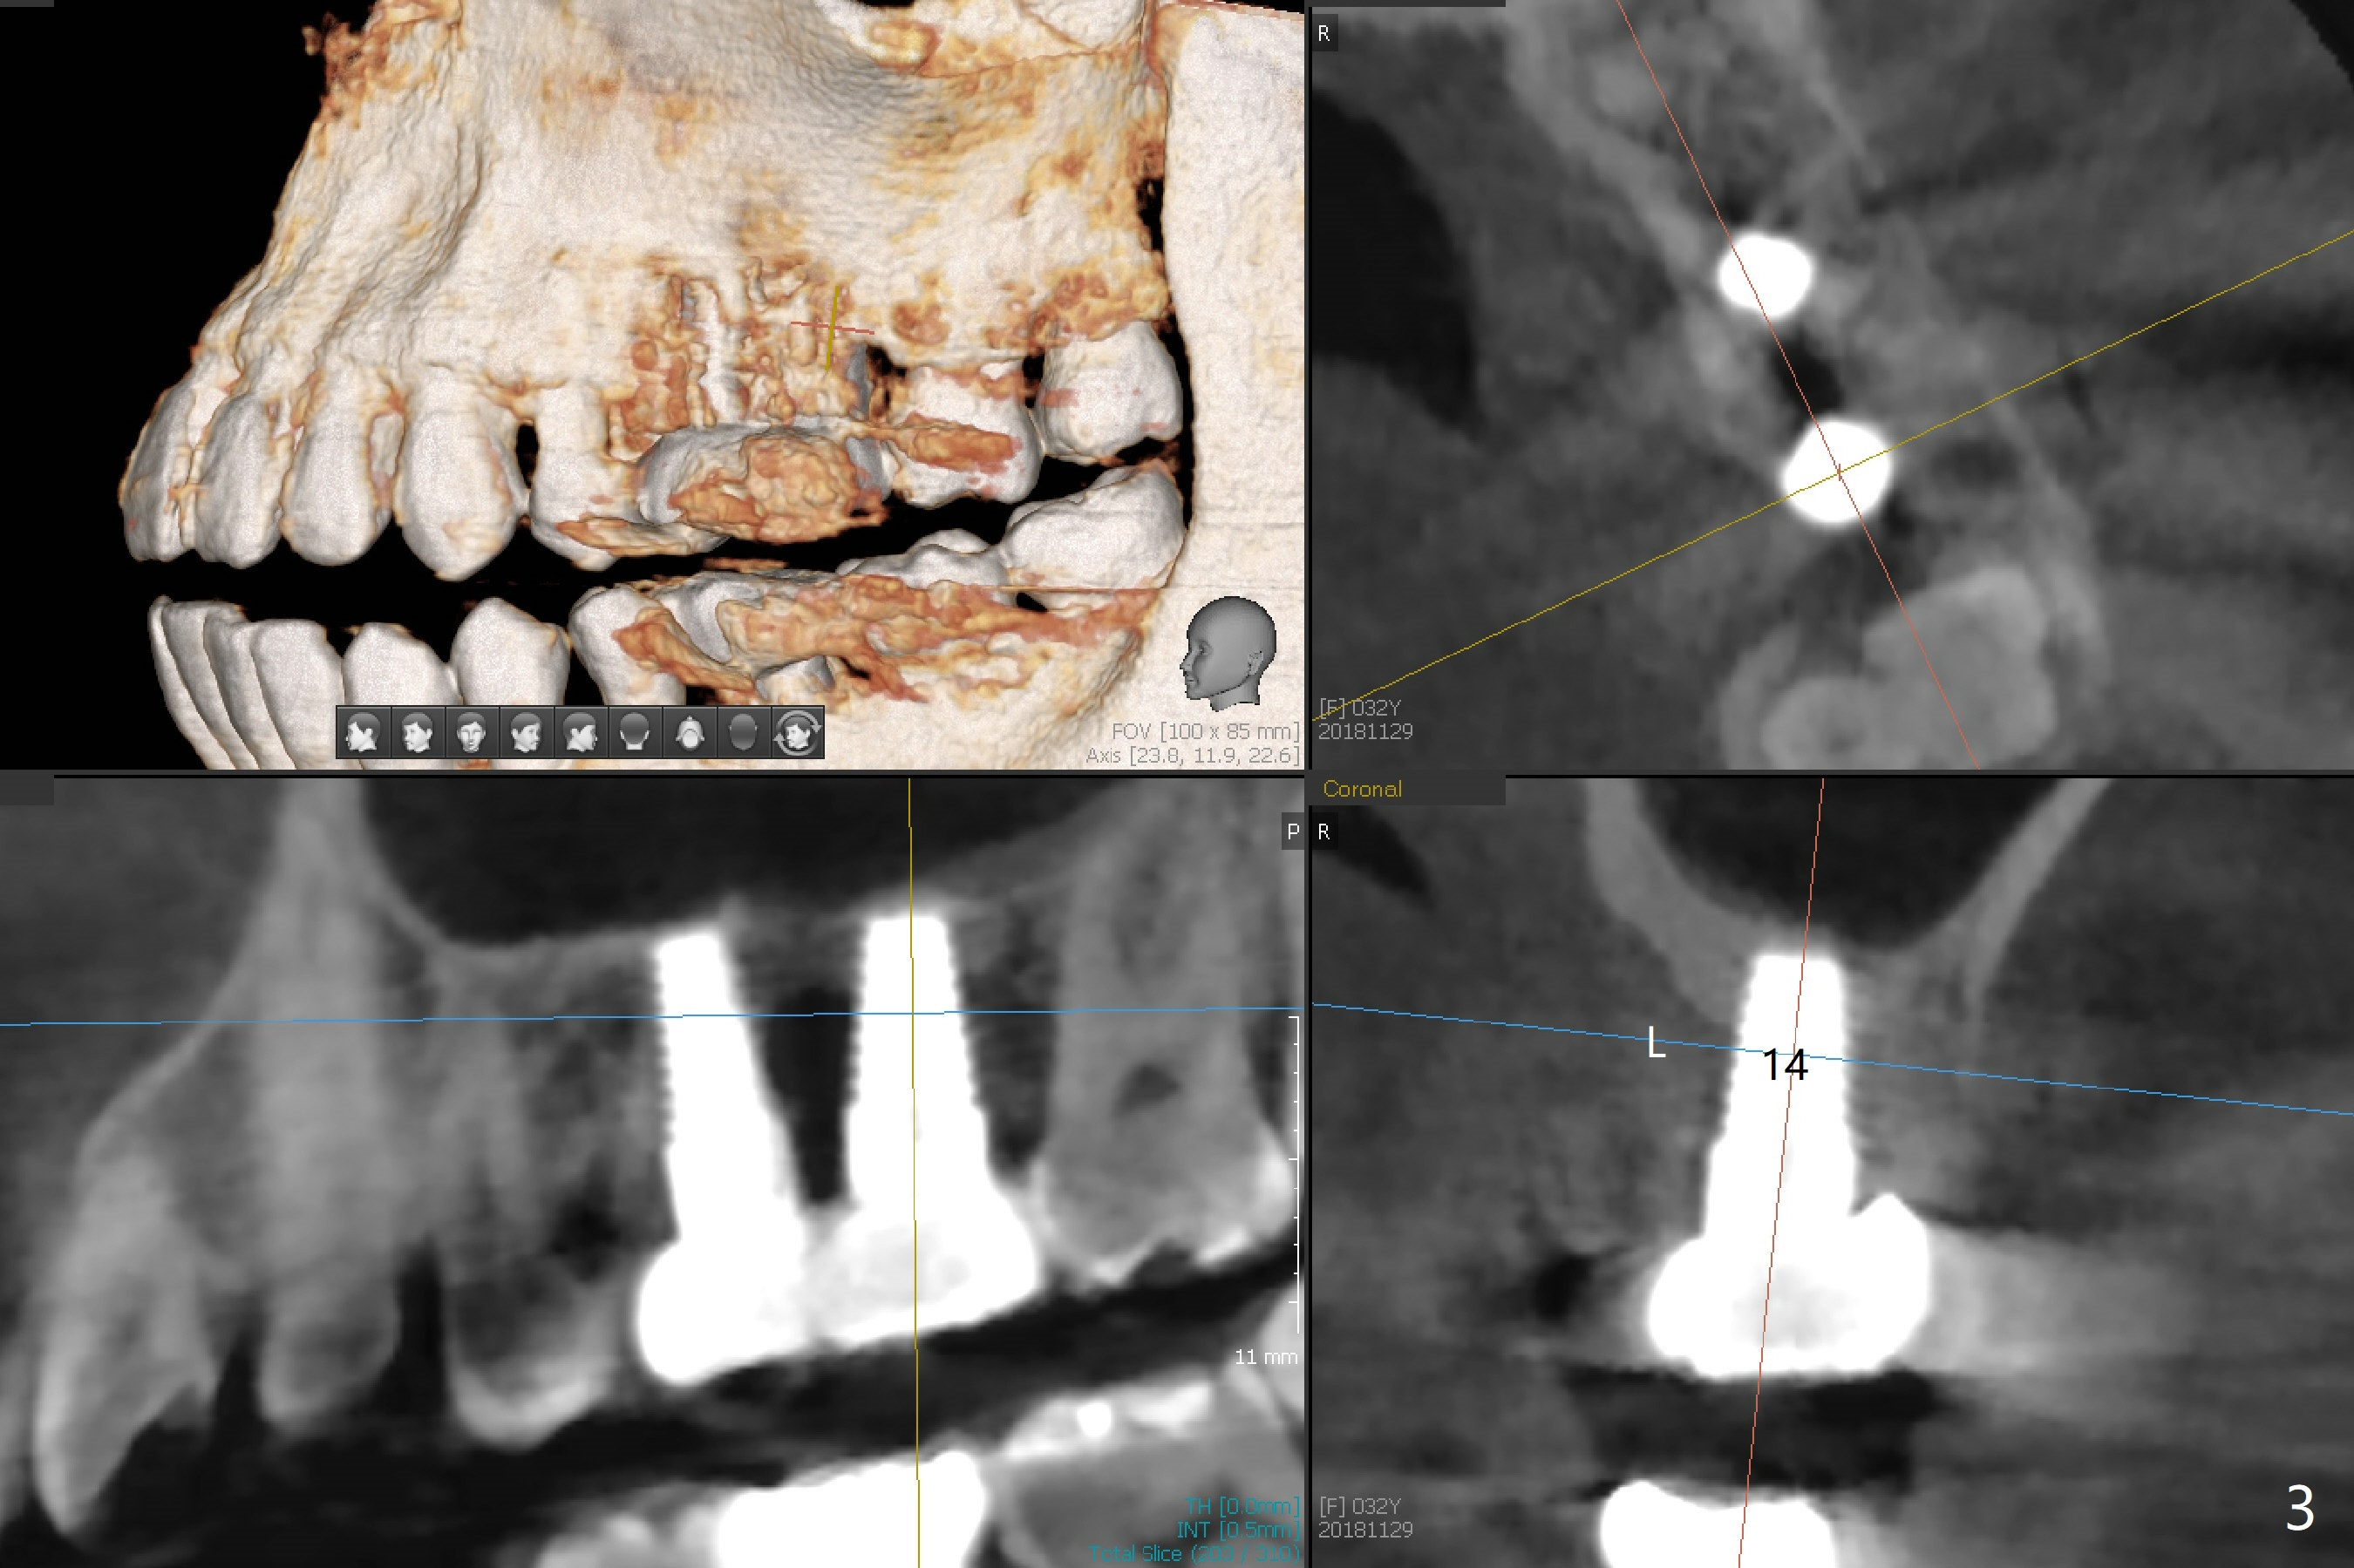

A 32-year-old woman develops periimplantitis (severe hemorrhage and deep pockets) at #14 three years 7 months post cementation (Fig.1).  A 4.5x11 mm implant is placed with flap at #13 after failure for the 1st time (Fig.2), while a 5x11 mm implant is placed flapless with sinus membrane perforation.  Uniposts are cemented with Ketac.  The lingual plate at #14 is defective (Fig.3).  The implant at #14 will be removed flapless, followed by Osteogen plug (most likely sinus floor defect) and bone graft.  After healing, an implant will be placed with guide.  By breaking the proximal contacts, the crown, abutment and implant at #14 are shaken loose using forceps.  Finally the crown breaks off.  Make a slot on the top of the abutment and use a screw bit to turn the abutment/implant counterclockwise.  There is abundant granulation tissue with arterial hemorrhage associated with granulation tissue removal.  The defect involves the distal surface of the implant at #13 and the mesial surface of the tooth #15.  Therefore bone graft is deposited in these surfaces (Fig.4 arrowheads, as compared to preop BW, Fig.4').  The periodontal dressing seems to remain in place asymptomatic 7 days postop (Fig.5).  The bone height 5.5 months postop should be enough for implantation (Fig.6).  To avoid marker associated with guided surgery, free hand will be adopted.  Sinus lift with PRF is expected.  To place in the middle of the ridge buccopalatally, incision will be made with bone expansion.